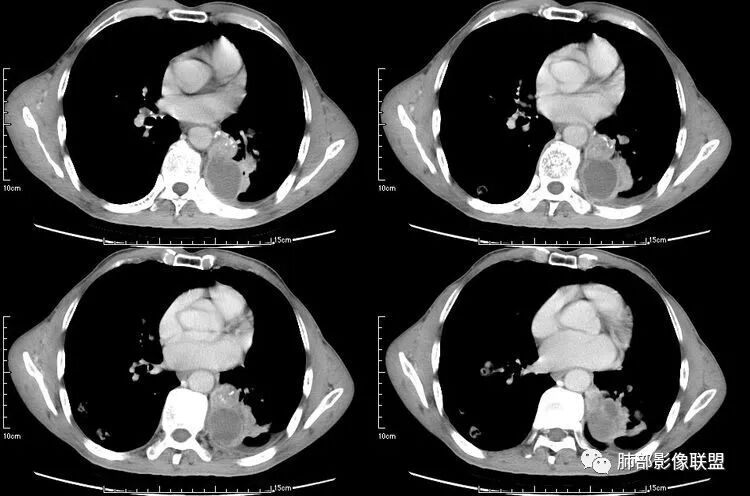

患者老年男性,咳嗽、咳痰、痰中带血伴胸闷2月余。长期大量吸烟史。查肝肾功能、血糖、血脂、心肌酶、电解质、血沉、C反应蛋白、抗“O”、类风湿因子、抗核抗体谱无明显异常。肿瘤标志物提示NSE、CYFRA21-1稍升高。胸部CT:肺气肿背景,左肺下叶后基底段不规则肿块影,见支气管截断,内见大片状低密度区及部分血管影,增强轻度强化,远端空洞形成。双肺多发不规则实性结节影、见毛刺、胸膜牵拉及血管集束,结节内见空洞形成,部分可见血管影,多位于胸膜下。双肺见多发肺大泡。综合考虑左下肺恶性病变并双肺转移。鳞癌或淋巴瘤可能。鉴别血管炎性病变及真菌感染。

左肺下叶团块病灶,有明显张力,增强后病灶内部有可疑延迟强化,看不清楚病灶与支气管的关系,应该支气管受压阻塞了,双肺多发胸膜下小结节,病灶小结节病灶有平行胸膜生长的表现,部分小结节厚壁,部分薄壁,,还有一部分有内容物,这需要两元论,左肺下叶肺癌(腺癌)伴转移,同时合并真菌感染。

无发热,其他慢性细菌先不考虑,有的低毒的,但是结节形态还是比较不规则的,分布也是比较随机,更像原发病灶。真菌方面,结节没有融合,坏死也是液化坏死,不符合隐球菌,曲霉不符合IPA,慢性吸入的也少见。结核没有树丫,不考虑。鉴别主要是GPA,和肺癌。GPA不支持点是皮肤,肾脏没有累及,ANCA不支持。。。肺癌主要是腺癌和鳞癌转移。比较支持的是淋巴结肿大,和左下肺的主病灶,支气管堵塞和异常强化。还有分叶,局部膨隆。可以建议支气管镜检测。

本病例左肺下叶肿块,有深分叶、毛刺、胸膜牵拉凹陷、支气管截断及纵隔内淋巴结肿大等征象,都均支持病灶为恶性,如腺癌,而且叶间裂的多发结节也提示是腺癌来源可能大;双肺多发结节、肿块,大部分病灶有分叶、毛刺及胸膜凹陷的恶性征象,与原发肿瘤本身的性质有关,所以应该与左肺下叶肿块同源,而且双肺多发病灶内空洞也具有多样性;

此病例中空洞形态多样,内壁不光整,有分隔影,周围未见明显卫星灶及钙化灶,结核不太符合;患者病史慢性病史,无明显发热,缺乏中毒临床表现,急性感染基本排除;各种中性粒细胞胞浆抗体阴性,没有鼻窦炎,肾脏等病史,基本排除血管炎;霉菌性空洞常见于免疫机能低下者, 常为空洞、肺炎、伴“ 晕圈”征的结节及支气管扩张合并存在。